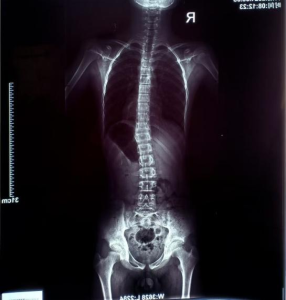

▪️ 问题类型:脊柱侧弯,Cobb角18°

▪️ 影像学报告:

康复前后对比

经过两个多月每周两次的系统性训练,目前进展成果如下:

(胸段16°到近乎0°;腰椎10°到6°)